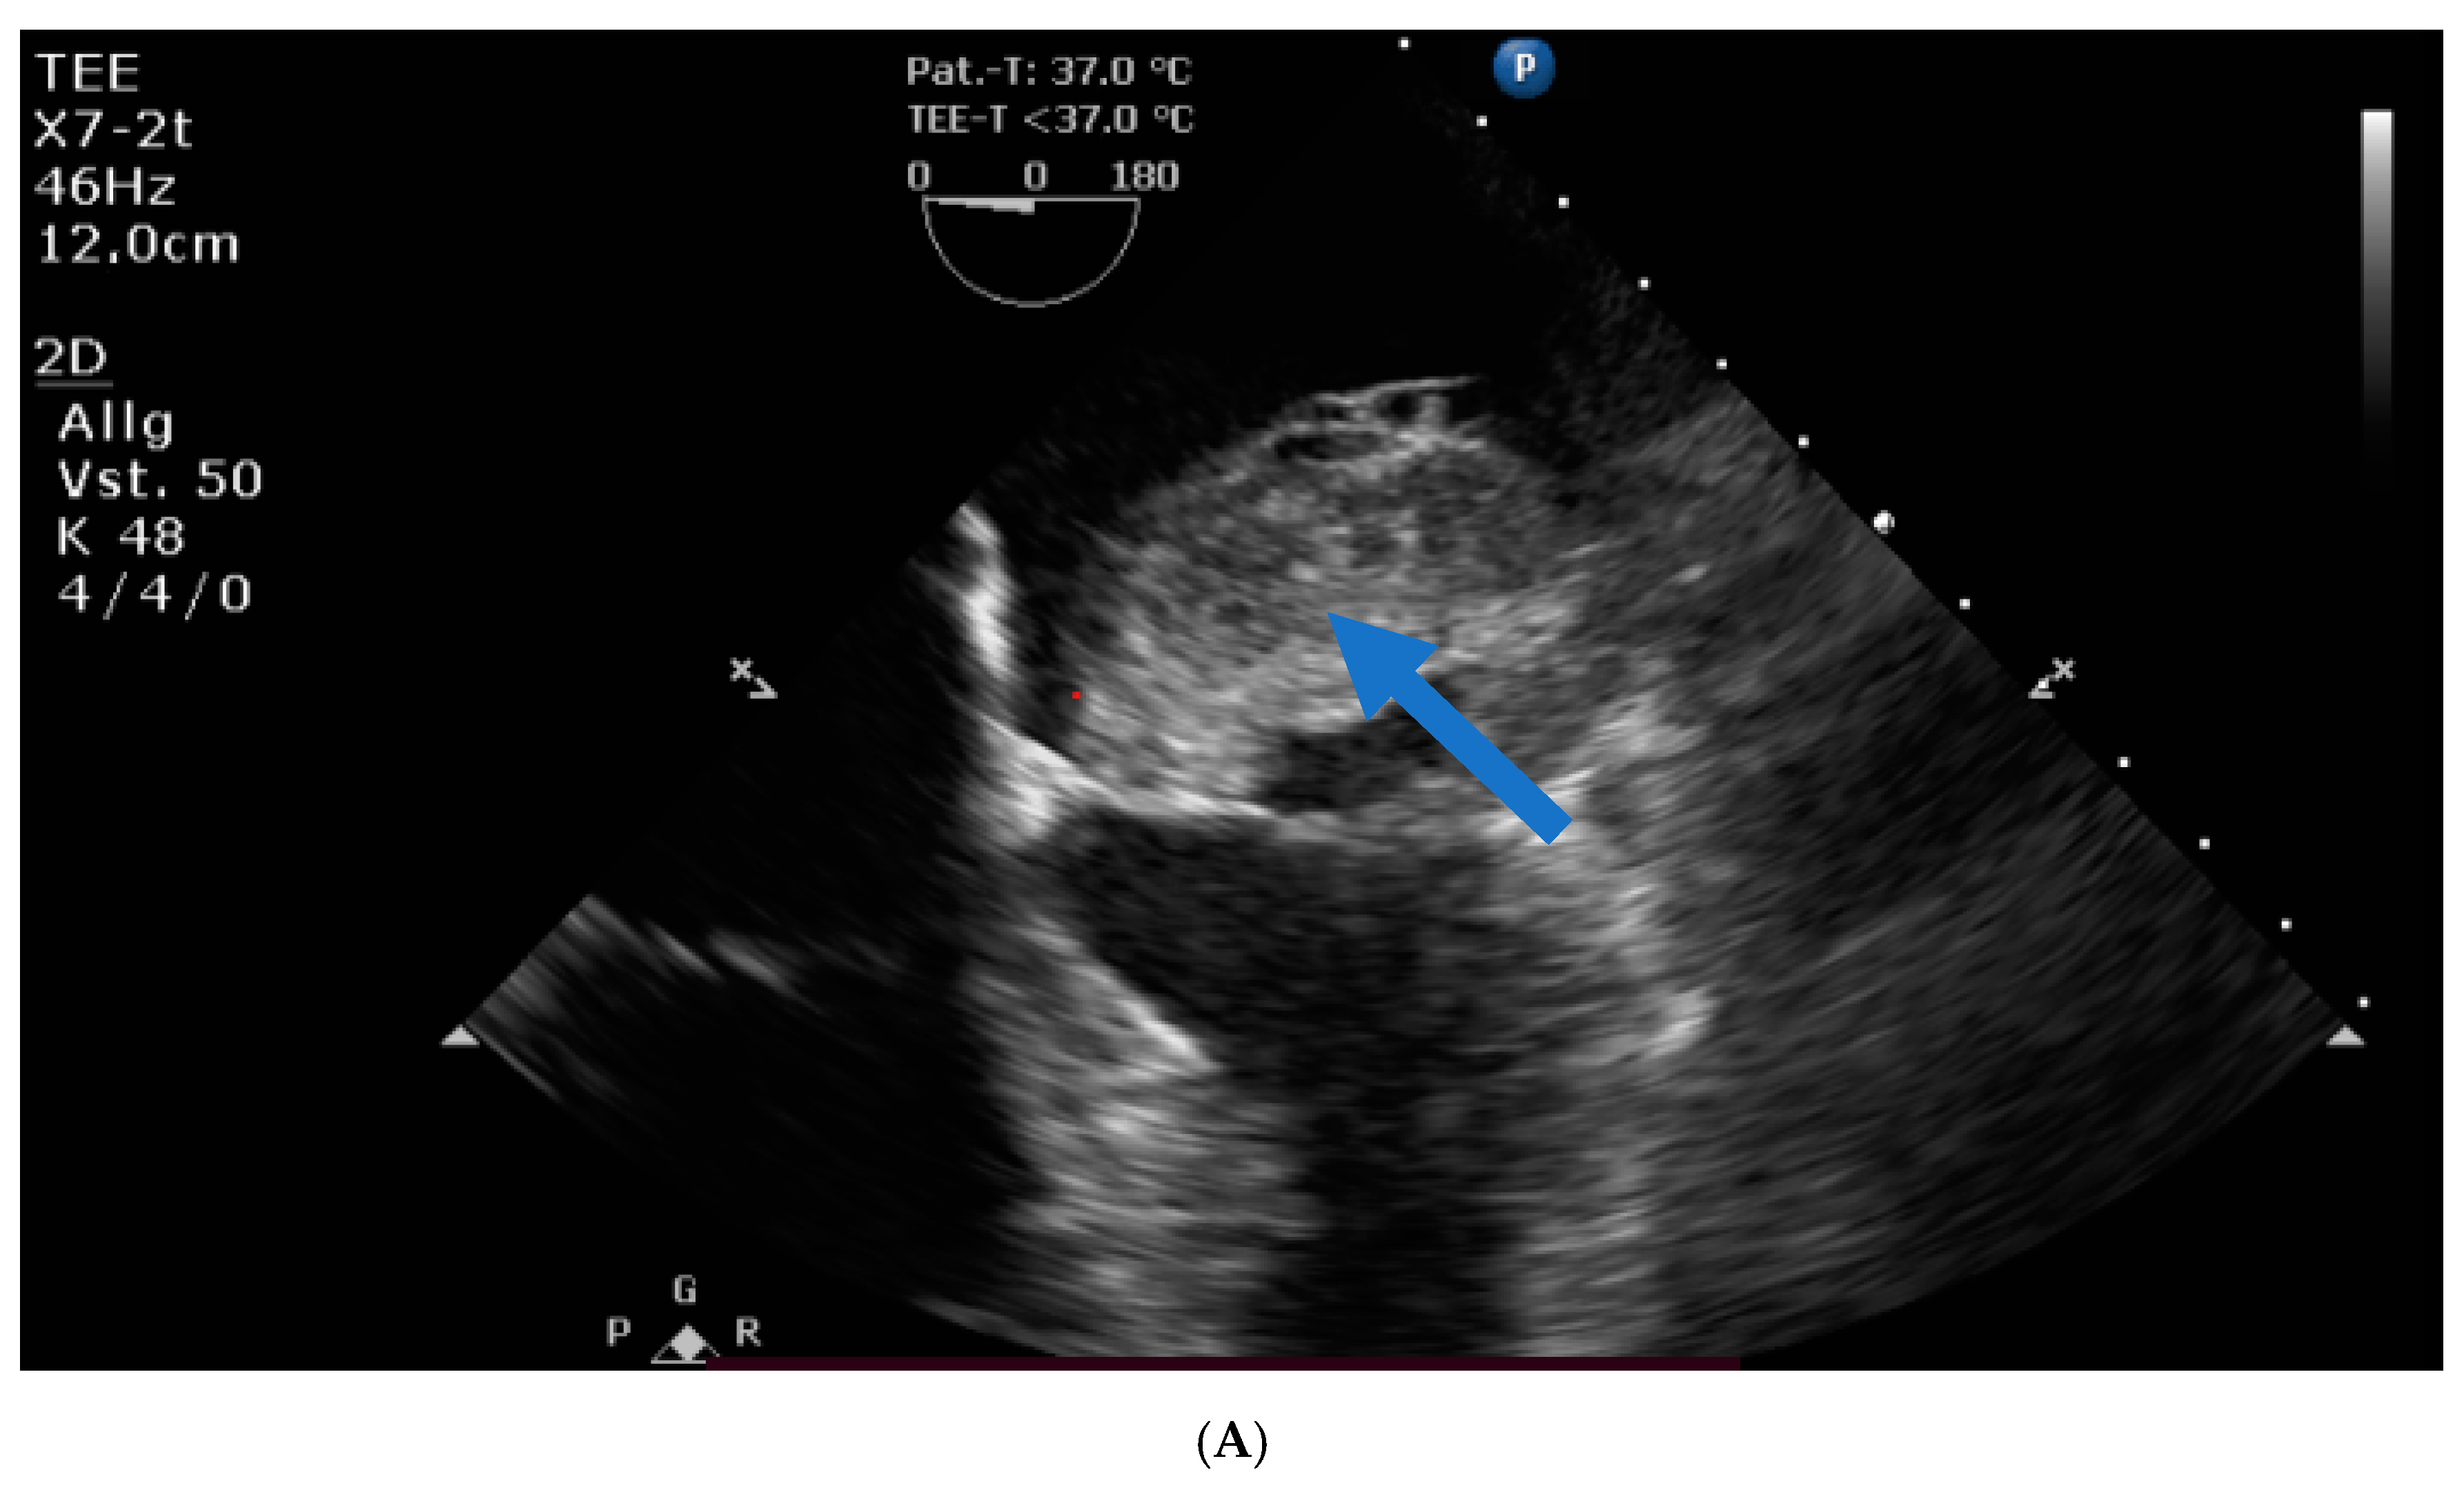

Transthoracic and transesophageal echocardiography revealed a large mass (40 × 60 × 24 mm) in the left atrial lateral wall, extending to the mitral valve (Figure 1A,B). Both atria were severely dilatated. The left ventricle was normal in size with an ejection fraction of 55%, an apicolateral/midlateral hypokinesia and a mild diastolic dysfunction. The normal-sized right ventricle had impaired systolic function. A hemodynamically irrelevant pericardial effusion was present.

Figure 1. (A) Huge left atrial mass (arrow indicates cardiac mass). (B) Huge left atrial mass prolapsing into the mitral valve in diastole and thus obstructing the inflow of the left ventricle (arrow indicates cardiac mass).